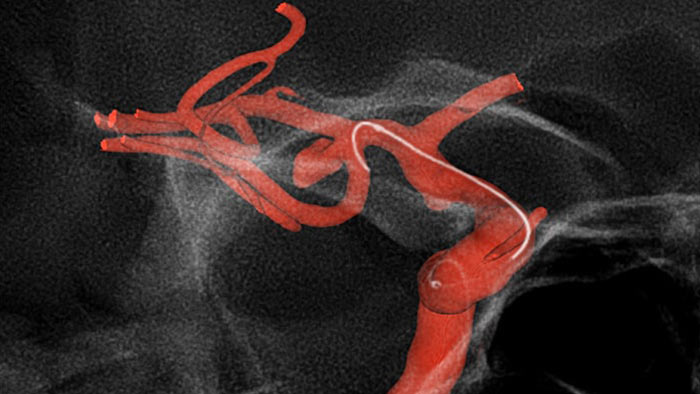

SmartCT Roadmap verbessert die Darstellung überlappender Gefäße und unterstützt so die präzise Navigation von Führungsdraht und Katheter durch komplexe Gefäßstrukturen. Die Echtzeit-Kompensation von Gantry-, Tisch- und kleineren Patientenbewegungen sorgt für ein hohes Niveau an Präzision.

Roadmap Pro, eine moderne Doppelkontrast-Roadmap, verbessert die Darstellung überlappender Gefäße bei gleichzeitigem Management der Strahlenexposition. Sie kann individuell angepasst werden, um das Vordringen beim Platzieren des Coils sichtbar zu machen.